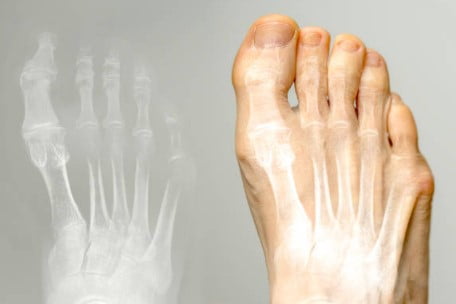

Deformacje palca V, czyli najmniejszego palca stopy, są powszechne w znacznej części populacji, ale tylko u niewielkiego odsetka osób objawy kliniczne są widoczne. Do najczęstszych zniekształceń należą palec młotkowaty i palec młoteczkowaty. Innym typowym zaburzeniem dla palca V jest nakładający się palec piąty, który jest uważany za wrodzony. Jest to deformacja charakteryzująca się podkurczonym bliższym paliczkiem i przywiedzionym stawem śródstopno-paliczkowym, co powoduje, że palec nakłada się na palec czwarty. Przyczyną tej deformacji mogą być osiowa rotacja paliczków proksymalnych, przyśrodkowe odchylenie palca, przykurcz skóry i zniekształcenie stawu MTP w wyniku przykurczu ścięgna prostownika. Chociaż deformacja ta może występować bezobjawowo, pacjenci często odczuwają ból podczas chodzenia, który wynika z ucisku piątego palca między czwartym palcem a butem.

Innym typowym zniekształceniem dla palca V jest podwijający się palec piąty, który również uważa się za zaburzenie o podłożu genetycznym. Zazwyczaj zauważa się go u dzieci we wczesnym okresie dzieciństwa, a bliższy paliczek u podstawy palców jest zwykle w szpotawości, a w stawie śródstopno-palcowym występuje zgięcie. Często dochodzi również do nieprawidłowej rotacji, którą można zauważyć po ułożeniu paznokcia.

Deformacje palca V często koryguje się nieoperacyjnie, ale jeśli problem się utrzymuje i powoduje ból, zaleca się konsultację u specjalisty. Na początek stosuje się szyny, zmienia się obuwie, a także dobiera się specjalne wkładki ortopedyczne. W przypadku braku skuteczności tych metod stosuje się leczenie chirurgiczne, takie jak przezskórna tenotomia zginaczy, prostowników, kapsulotomia, przenoszenie ścięgien, osteotomie i artrodezy.